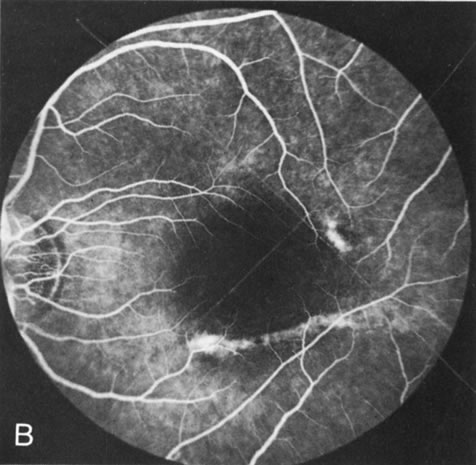

In the early stages of choroideremia, before choroidal atrophy is funduscopically obvious and when the picture resembles RP, FA indicates diffuse choroidal atrophy throughout the entire retina. Only the macular area remains preserved (Fig. 4A and B).

Fig. 4. Choroideremia and choroideremia carrier. A. The choroidal atrophy in this affected male is not apparent in the fundus. B. However, the angiogram shows diffuse atrophy of the choriocapillaris with persistent visualization of the larger choroidal vessels. C. This carrier female has peripapillary choroidal atrophy and diffuse pigment mottling. D. The patchy areas of focal choroidal atrophy that occasionally occurs in carriers is evident on angiography.

The typical carrier female, with focal or diffuse pigment mottling, does not show choroidal atrophy. However, a few carrier females have a more severe form with focal areas of choroidal atrophy. The presence of these areas, and possible progression, can be documented by FA (Fig. 4C and D). These carriers exhibit a mosaicism, which is explained by the Lyon hypothesis of random X-chromosome inactivation.